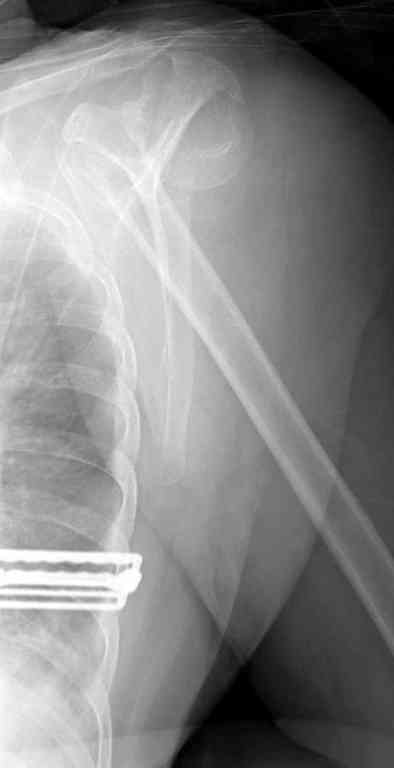

По Neer операцию рекомендовали только тогда, когда угол между диафизом и головкой составляет около 45 градусов, и переломы с меньшим углом смещения считали благоприятным для функционального результата.

Хотя "варусная импакция" в проксимальном отделе плеча срастается хорошо консервативными мерами, но в результате при восстановлении такие больные теряют часть отведения, и тем более у больной варус осложнен еще сгибанием.

Закрытые репозиции без фиксации из-за вторичного смещения неэффективны, поэтому рекомендуется репозиция с фиксацией. Методик много, кто чем владеет и отдает предпочтение закрытые-открытые, перкутанные, с блокирующими пластинами, гвоздь, множественными спицами или методом спиц по Лазареву, и осторожно с манипуляциями из=за возможности повреждения аксиллярного нерва - частый вид осложнении.

Неправильно выбранная тактика по фиксации или технические ошибки во время операции могут привести к серьезным осложнениям. Здесь привожу

пример из нашей практики, вроде обычный перелом шейки, фиксированный популярным методом "Сиэтла" - множественными спицами 2.8 мм с резьбой на конце.

При первичном осмотре в поликлинике через 3 недели обнаружили миграцию двух спиц, срочно госпитализированному на второй день перед операцией на всякий случай сделали снимок, одна спица находилась под ключицей в шейном отделе (на снимке).